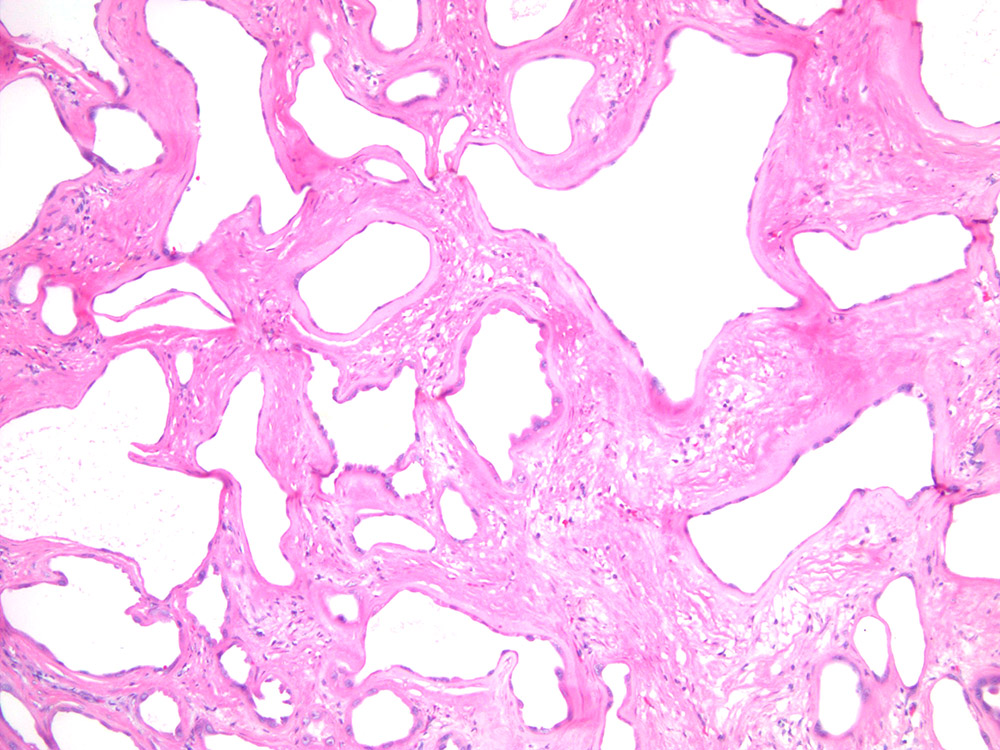

Consensus grade: Tubulocystic RCC

Renal mass- 62 year old woman